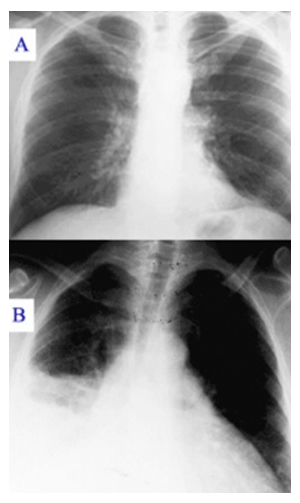

Pneumonične promjene (atipična pneumonija) su najčešća pojava kod hospitaliziranih bolesnika i javljaju se u 60%. Plućne promjene se razvijaju u obliku netipične pneumonije sa diskrepancom između diskretnog auskultatornog nalaza i sasvim jasnog radiografskog nalaza. Radiografski nalaz nakon nekoliko dana pokazuje nejasno ograničenu, meku sjenu, često multiplu ili obostranu, a prije svega u donjim plućnim režnjevima. Često se vide i natečeni hilusi. Plućne promjene se mogu podijeliti u 4 grupe:

- izolirani ili multipli infiltrati, mekani i podsjećaju na TBC proces. Ova forma je najčeća,

- masivne velike infiltracije, tzv. »Pseudo-lobarne pneumonije«,

- milijarni infiltrati, tzv. »pseudomilijarna tuberculosa« i

- perihilarni infiltrati »pseudo-bronho-karcinom«.